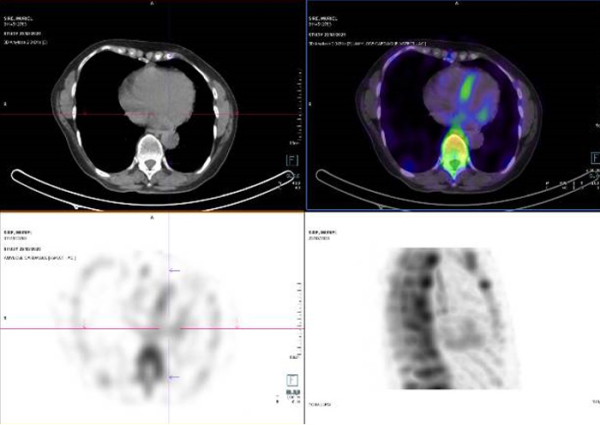

Figure 2 : scintigraphie corps entiers au DPD aux temps tardifs objectivant une hyperfixation cardiaque sans extinction de la trame osseuse (stade 2 de Perugini)

Figure 3 : coupes tomographiques cardiaques couplées à la scintigraphie corps entiers au DPD, confirmant l’hyperfixation du myocarde (et non pas du pool sanguin intracardiaque comme parfois observé en cas de ralentissement du flux sanguin).

Comme vous le voyez, les images de la scintigraphie, réalisées aux temps tardifs, mettent en évidence chez la patiente une hyperfixation de l’aire cardiaque sur les vues corps entier (Figure 2). L’évaluation est semi-quantitative et classée par le médecin nucléariste stade 2 de Perugini. Cette hyperfixation myocardique très caractéristique est ensuite confirmée sur les coupes tomographiques (Figure 3). Ceci est primordial car l’une des causes possibles de faux positif est la fixation du pool sanguin intracardiaque en cas de ralentissement du flux sanguin.

Comme souvent dans les atteintes précoces d’amyloses cardiaques à TTR, les anomalies prédominent ici au niveau de la paroi septale du VG et en latéral basal.